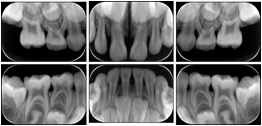

2. A patient requests cosmetic surgery to enhance their facial appearance. The case requires consultation between an orthodontist in New York and an oral surgeon in California. The cephalometric series of 2D projections constructed from the volumetric CT data that is used for the discussion is arranged by a Structured Display for transfer between the two practitioners.

Cephalometric Series Structured Display

Figure OO-2. Cephalometric Series Structured Display